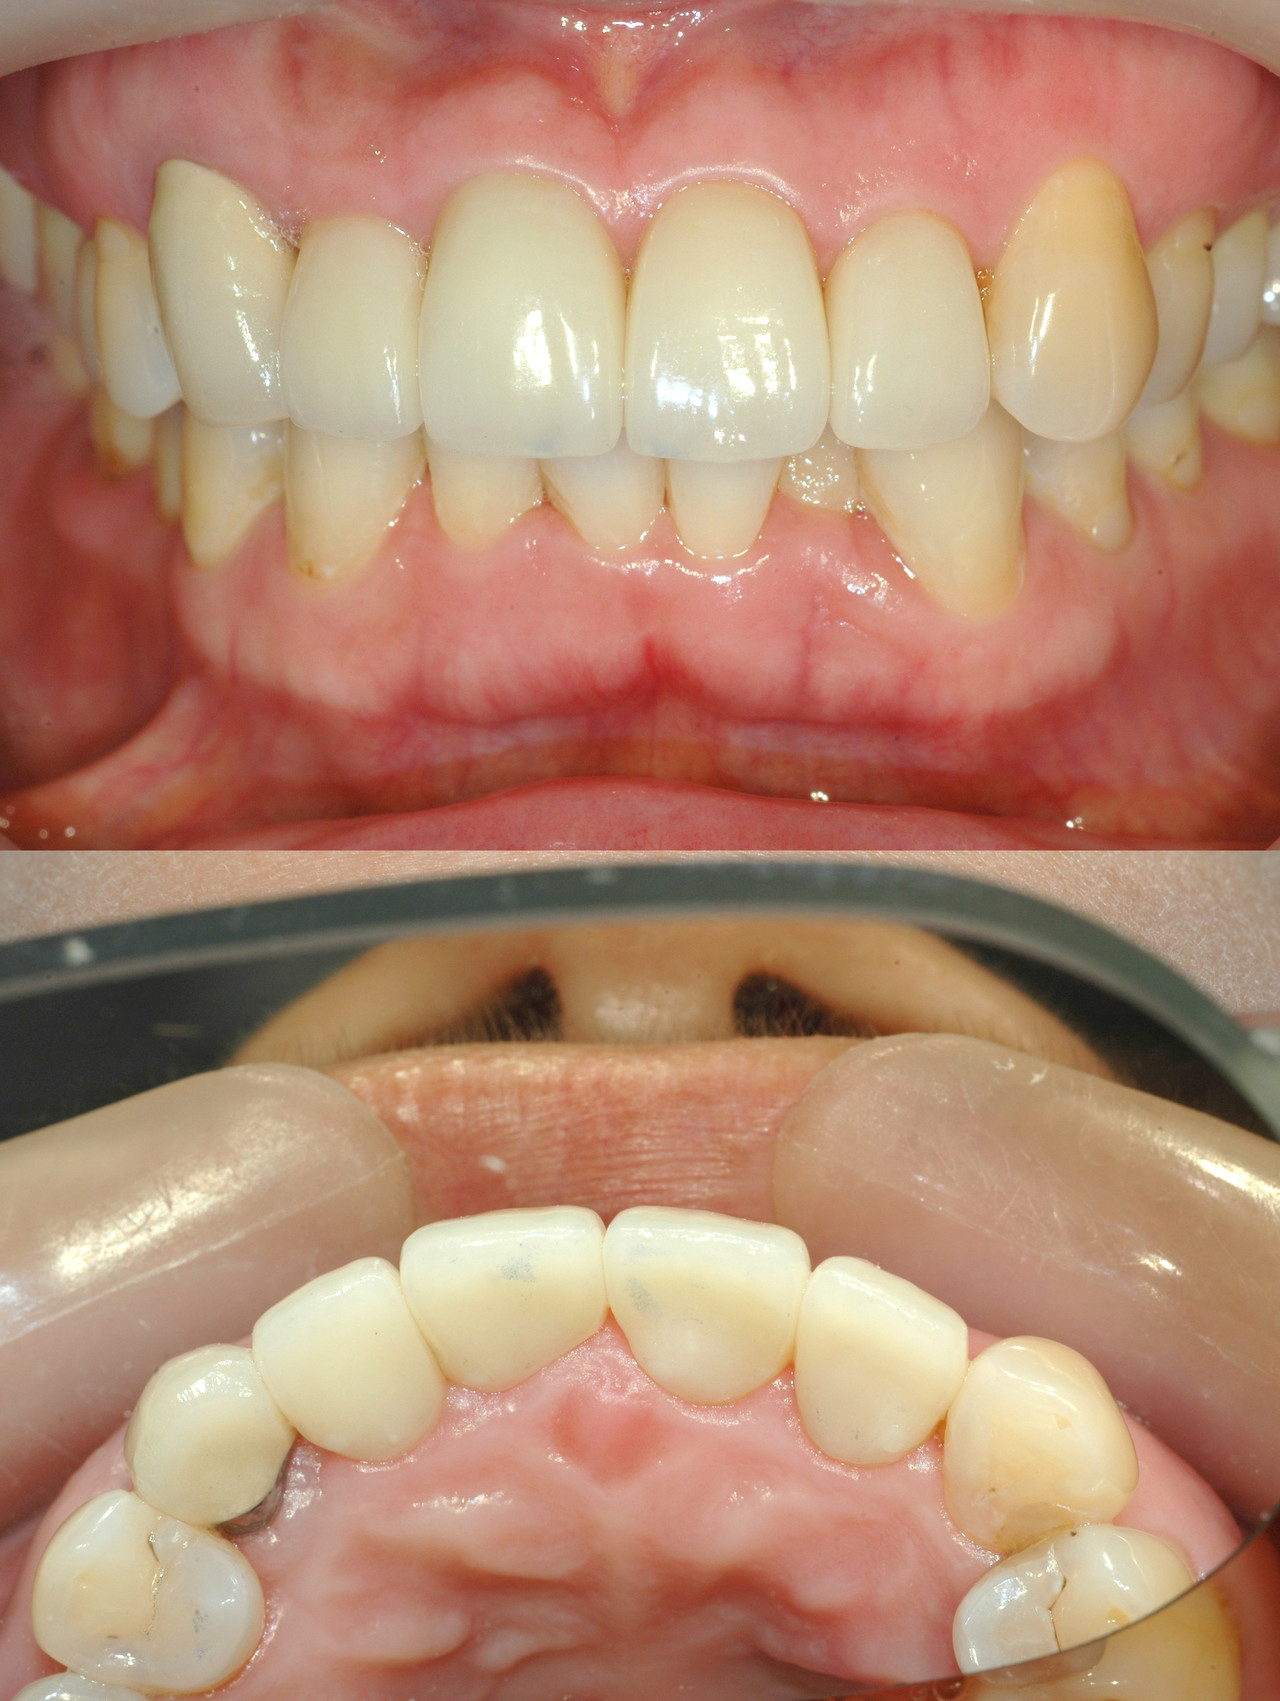

Before & After

> 토브 일반진료 사례

case 01

레진 치료

case 02

인레이 치료

case 03

전악보철

> 토브 협진치료 사례

교정+보철+치은이식

교정+임플란트

Before

라미네이트 시술 전

After

라미네이트 시술 후

올세라믹 크라운 시술 전

올세라믹 크라운 시술 후